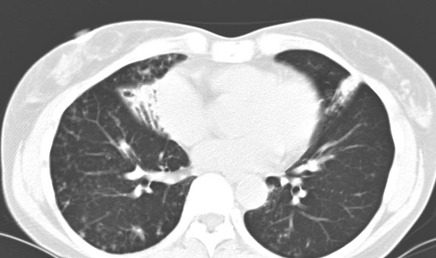

Klinisch zijn longinfecties door NTM zijn nauwelijks te onderscheiden van longtuberculose, hoewel het beloop doorgaans trager is. Van de twee radiologische te onderscheiden varianten van NTM-longinfecties is de holtevormende in Nederland veruit het meest frequent. Afwijkingen op longfoto’s en CT-scans zijn niet betrouwbaar te onderscheiden van longtuberculose (foto 1,2). De tweede radiologische variant, gekenmerkt door bronchiëctasieën en nodulaire afwijkingen in lingula en middenkwab (foto 3), is zeldzamer in Nederland. Mogelijk is het feit dat deze afwijkingen door NTM veroorzaakt kunnen worden nog niet erg bekend in Nederland; in de Verenigde Staten is deze ziektevorm veelvoor-komend, veel meer dan de klassieke holtevormende variant.

Foto 1: Röntgenopname van de thorax: holtevorming obv m.avium-infectie

Foto 2: CT- opname van de thorax: hotlevorming obv m.avium-infectie